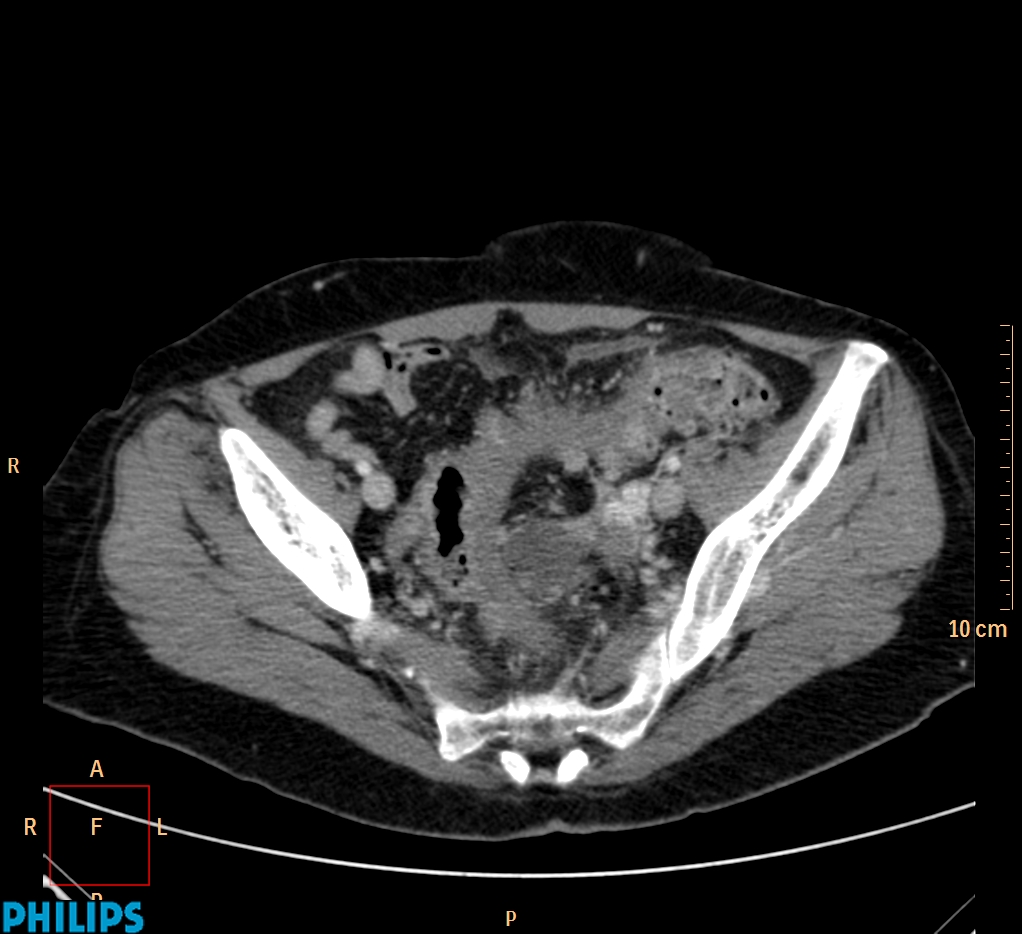

ΕΚΚΟΛΠΩΜΑΤΑ ΠΑΧΕΟΣ ΕΝΤΕΡΟΥ Posted by ΙΠΠΟΚΡΑΤΕΙΟ ΙΩΑΝΝΙΝΩΝ | Dec 16, 2020 | ΠΕΠΤΙΚΟ | 0 ΚΛΙΝΙΚΑ ΣΤΟΙΧΕΙΑ – ΙΣΤΟΡΙΚΟ υποτροπιάζοντες επαναλαμβανόμενοι πυρετοί κυρίως απογευματινές ώρες ΕΡΓΑΣΤΗΡΙΑΚΟΣ ΕΛΕΓΧΟΣ ΑΠΕΙΚΟΝΙΣΤΙΚΟΣ ΕΛΕΓΧΟΣ διακρίνονται τα αποστήματα στην ελάσσονα πύελο, καθώς και εκκολπώματα με εικόνα πάχυνσης του τοιχώματος του σιγμοειδούς ΣΥΖΗΤΗΣΗ